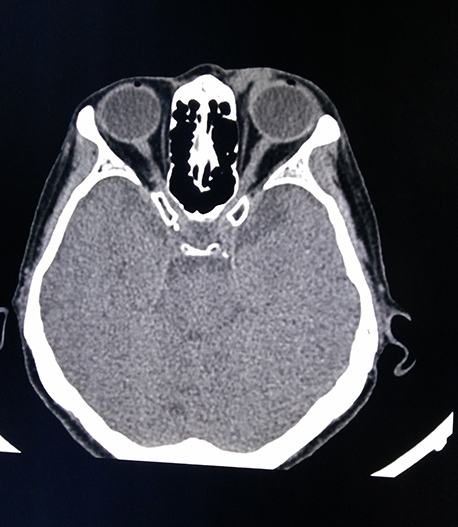

醫(yī)學影像科現(xiàn)有醫(yī)務(wù)人員15名,其中主任醫(yī)師2名、主治醫(yī)師3名。學科帶頭人張鐵英主任醫(yī)師、教授,曾任舟山市醫(yī)學會放射學分會主委,應(yīng)用影像新技術(shù)對人體各系統(tǒng)進行檢查及疾病診斷,尤其是對神經(jīng)系統(tǒng)、呼吸系統(tǒng)、消化系統(tǒng)、骨關(guān)節(jié)及肌肉系統(tǒng)疾病的影像診斷有較高造詣。醫(yī)學影像科7×24小時開放,為醫(yī)院門診、急診及住院患者提供優(yōu)質(zhì)、高效、迅速的影像診療服務(wù)。